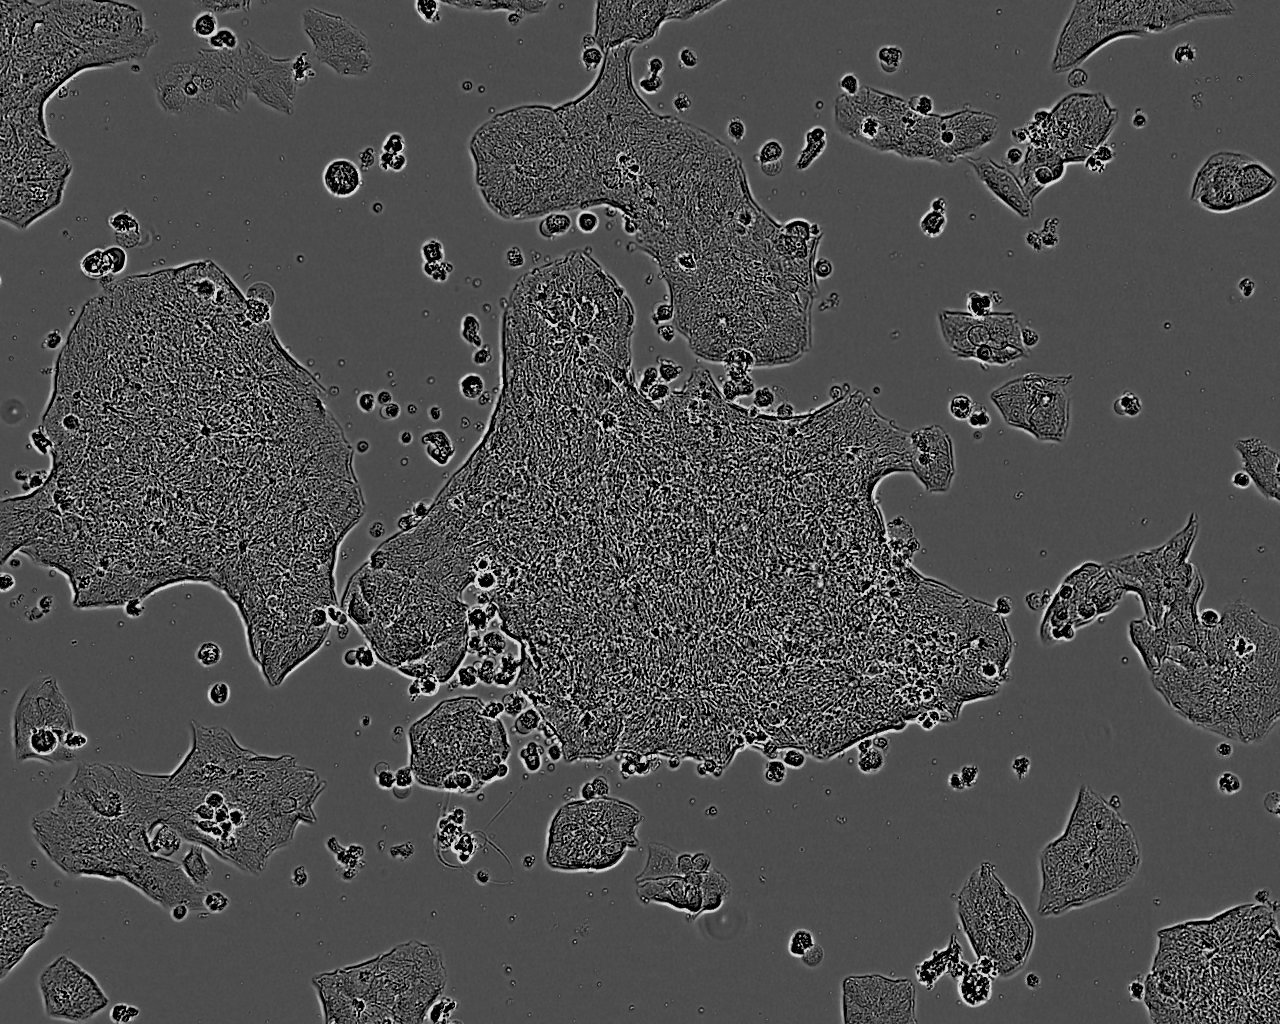

细胞生长:贴壁

细胞形态:上皮细胞样

细胞生长特性:贴壁或悬浮,详见细胞说明书部分